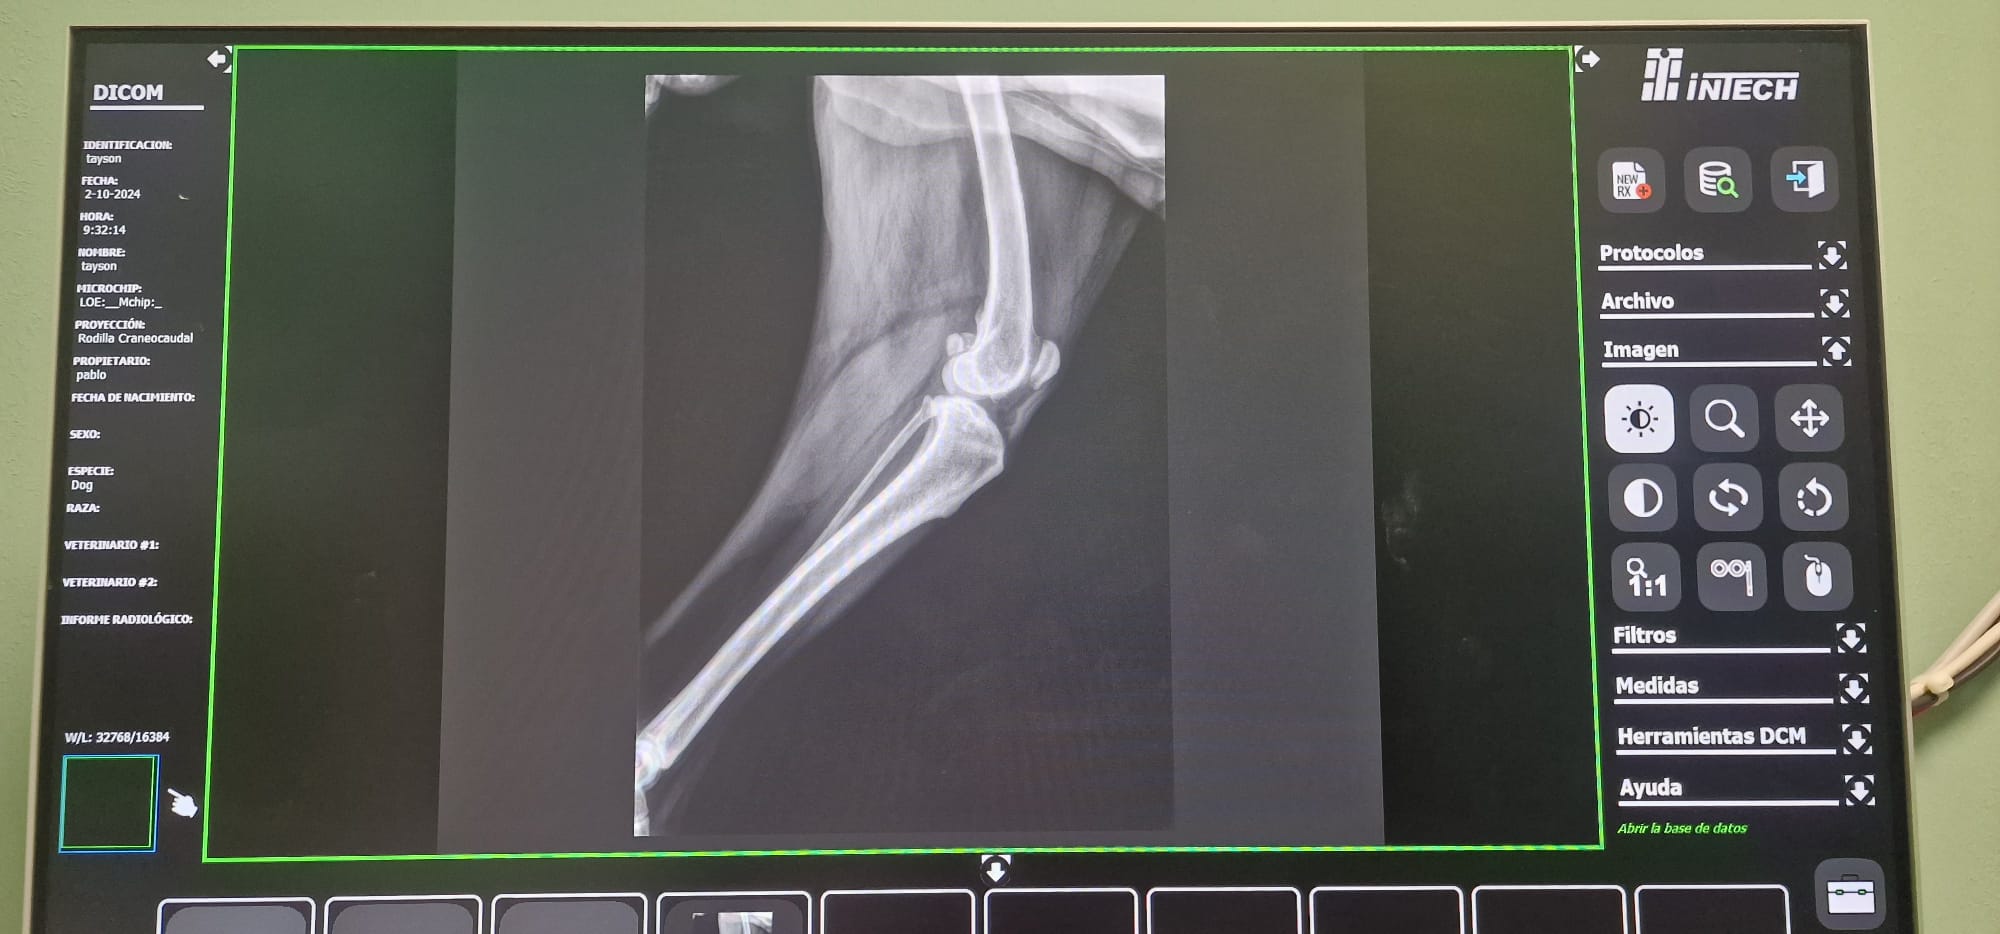

Radiografías = Salud en Imágenes 🐾🩺En Smile Vet, ofrecemos servicios de radiografías para cuidar la salud de tu mascota con precisión y cariño.

• Diagnóstico Rápido: Las radiografías nos permiten detectar problemas (óseos, dentales, respiratorios, cardiacos, etc.) y cuerpos extraños sin procedimientos invasivos. 🐶🐱

• Tecnología Avanzada: Utilizamos equipos modernos para obtener imágenes claras y detalladas, asegurando un diagnóstico eficaz.

• Cuidado Integral: Nuestro equipo interpreta los resultados para ofrecerte el mejor plan de tratamiento, siempre con el bienestar de tu mascota como prioridad. 🐾